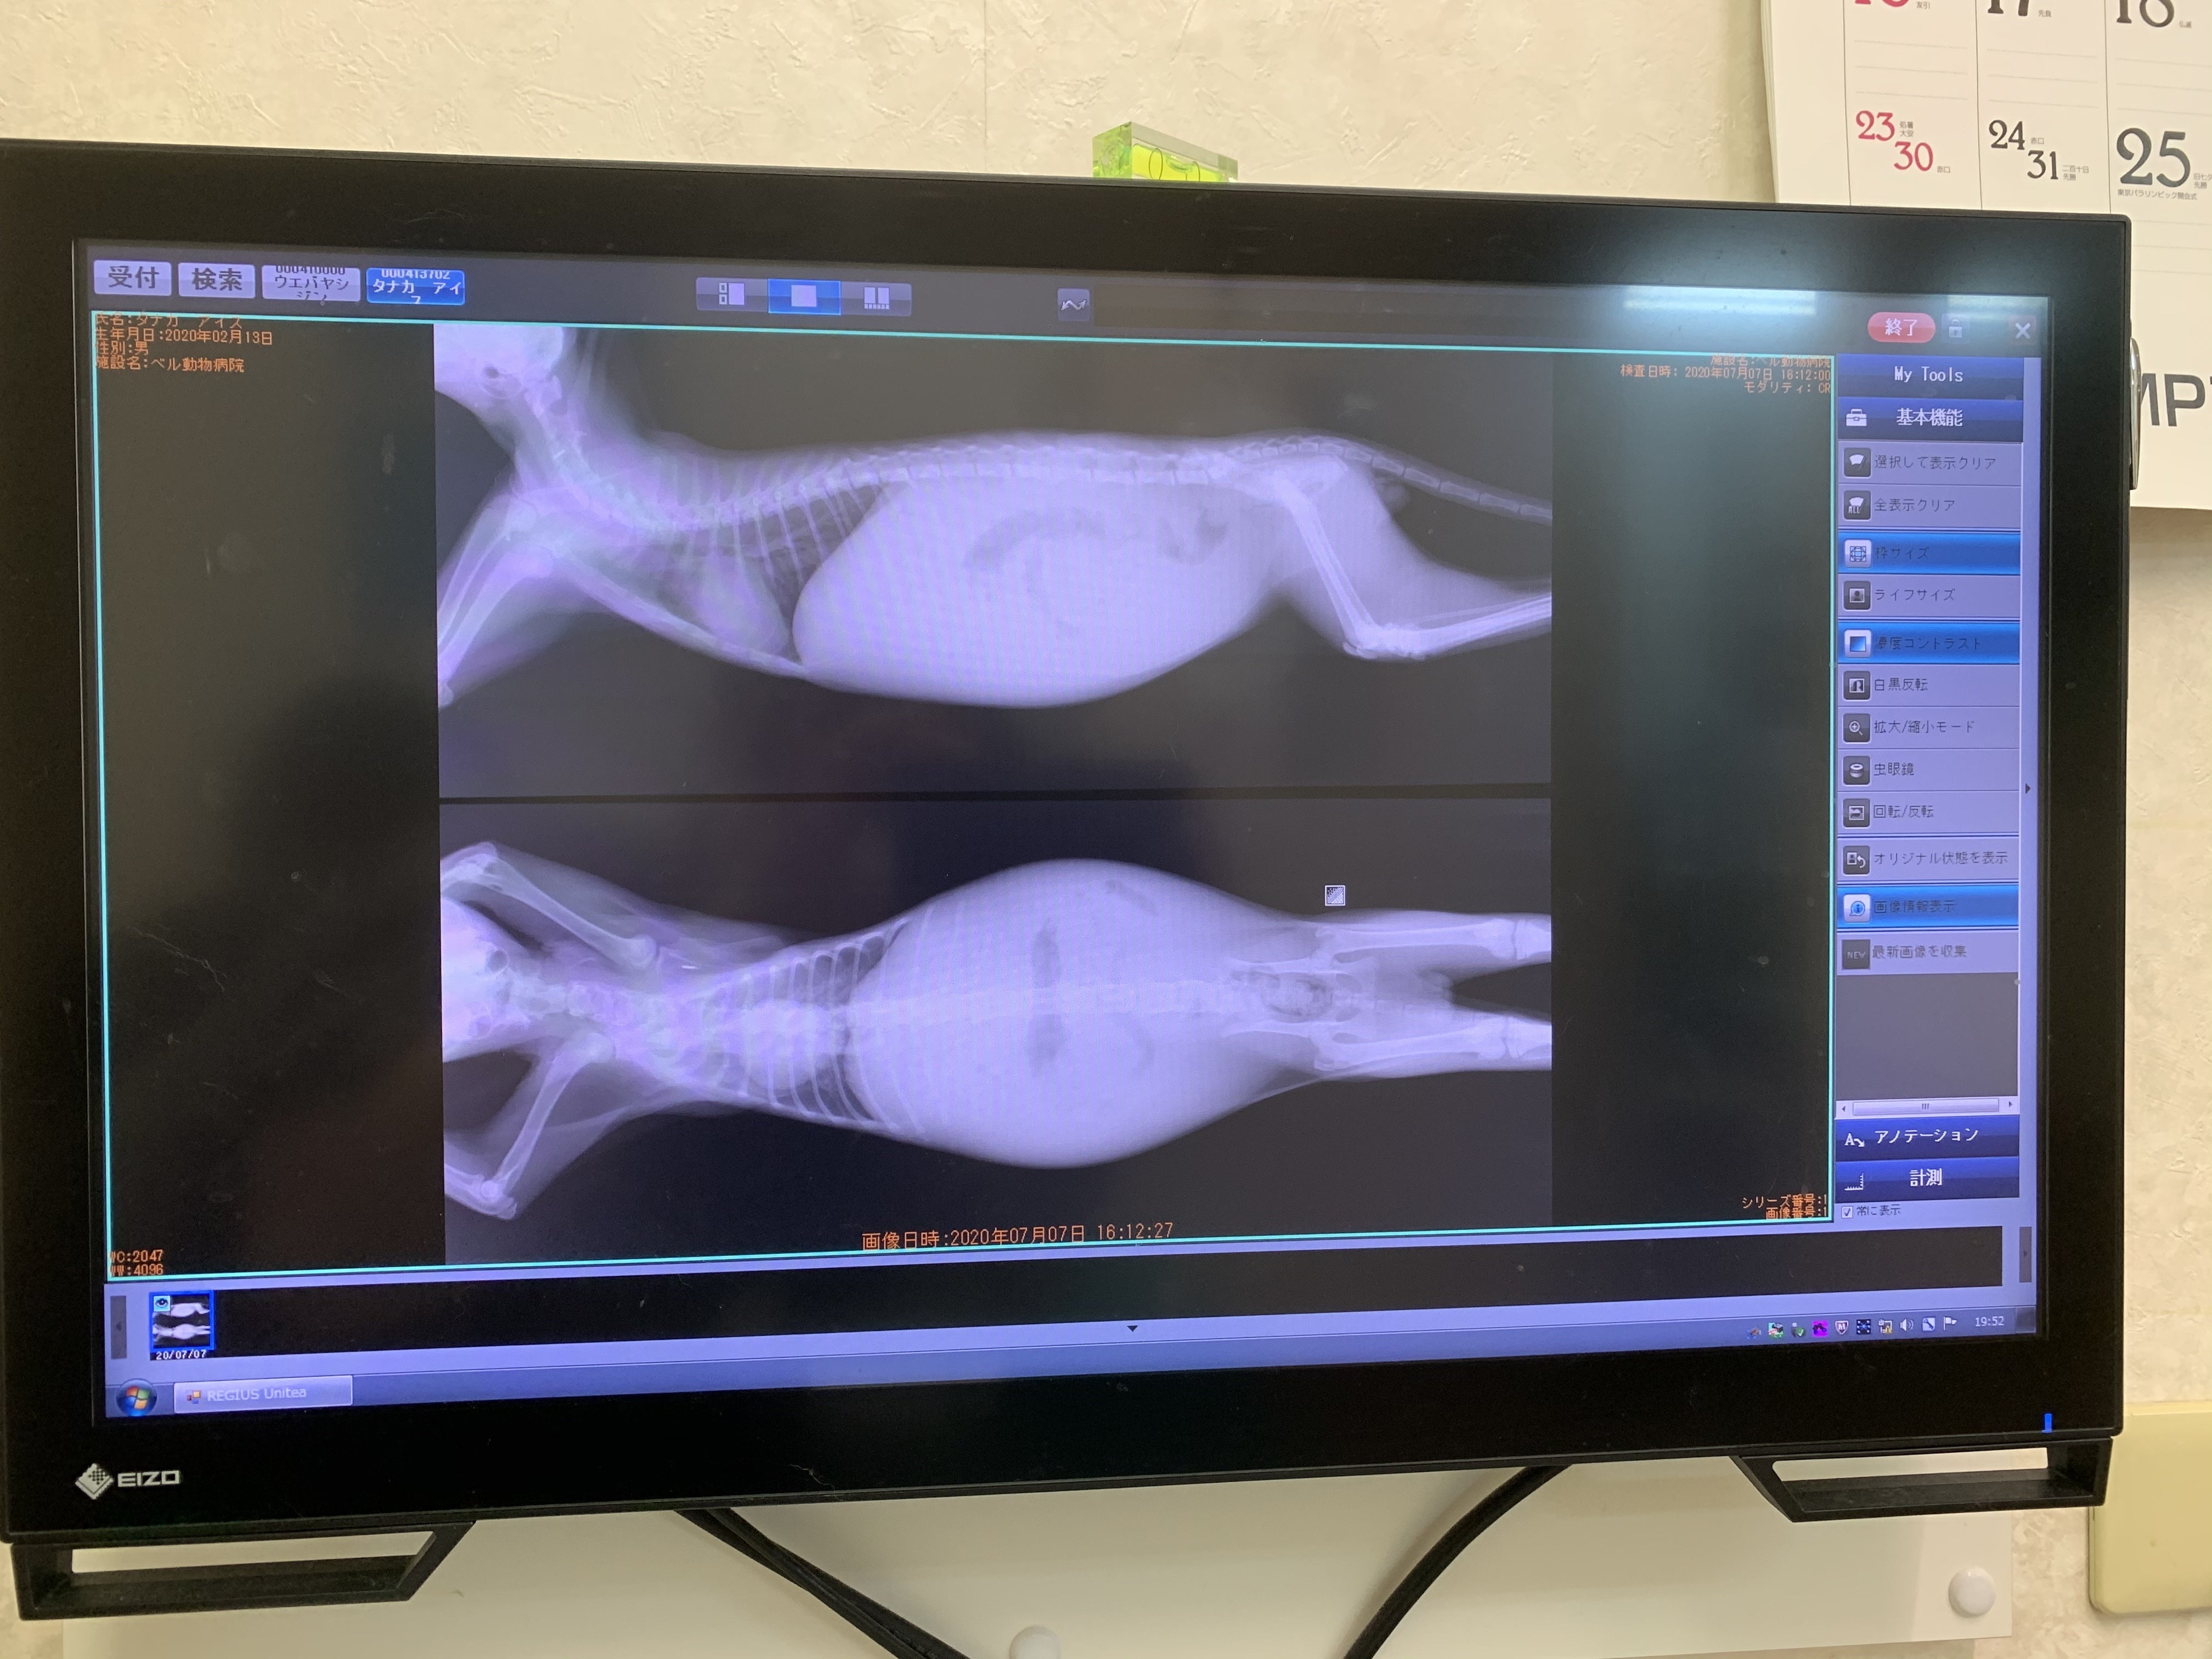

腹水の溜まっているアイス君レントゲン画像

とても食いしん坊で、いつもみんなからご飯を横取りしちゃう様な、やんちゃなアイス君でした。みんなから愛されスクスク育ってくれていると思っていたのですが、我が家に来て3ヶ月が過ぎた頃の7月初旬、ワクチンの後、発熱が続き、お腹の膨らみも気になり病院へ連れて行くと猫伝染性腹膜炎(FIP)の疑いがあると言われました。

結局、お腹の膨らみは腹水でした。

現在猛威を奮っている新型コロナウイルスとは違い、人には感染しませんが、FIPはとても致死率が高く、早くて数日長くても2ヶ月で亡くなってしまうと余命宣告されました。ウエットタイプとドライタイプがあるのですが、アイス君はウエットタイプであろうと言われました。確定診断が出るまでの一週間を待たずに食いしん坊だったアイス君はご飯を食べなくなりました。腹水も溜まりお腹がパンパンになってきていました。他の猫とも遊ばなくなり、いつも寝ている様になりました。この間、ステロイドとインターフェロンの注射の治療はしていましたが、延命できるだけで治るわけではないとかかりつけ医からは言われていました。